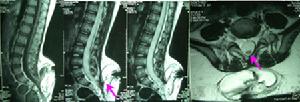

2.CT、MRI掃描顯示脊柱裂及脊髓、神經的畸形,以及局部粘連等病理情況。

MRI檢查:能顯示囊內的脊髓和神經根並能發現突出常伴有的其它畸形如脊髓栓系椎管內或皮下脂肪瘤皮樣囊腫或表皮樣囊腫等。